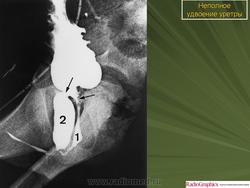

5. Удвоение уретры.